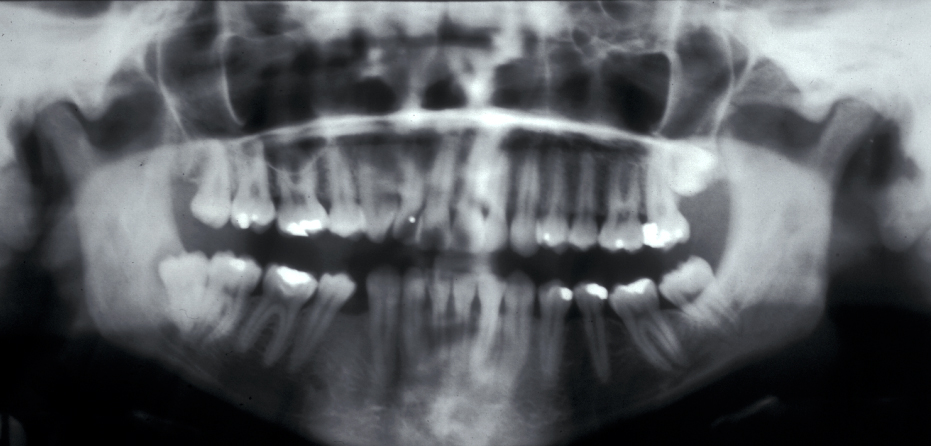

Assessment of the tooth is both clinical and radiographic. If somebody presents in pain, it is important to establish that this is coming from the third molar and not elsewhere. Pain is often vague, poorly localised and may be referred from another tooth, or as part of facial arthromyalgia (condition affecting the jaw joint). A dental panoramic radiograph is ideal as it helps to assess all the teeth at once. The health of the adjacent molars may influence the decision whether to remove the third molar or not. Large crowns or old restorations are all at risk of dislodgement during surgery. It is also worth considering whether alternative treatment options are available. For instance, pericoronitis due to an over-erupted upper third molar may be dealt with by extracting that tooth only, with or without operculectomy. In the presence of other teeth of poor prognosis, will it be better in the long term to save the third molar which may be used as a denture or bridge abutment in the future?

These points help to determine whether the tooth can be simply elevated or will need a surgical approach. A series of radiographs depicted in Figure 4 to Figure 8 illustrate these points further.